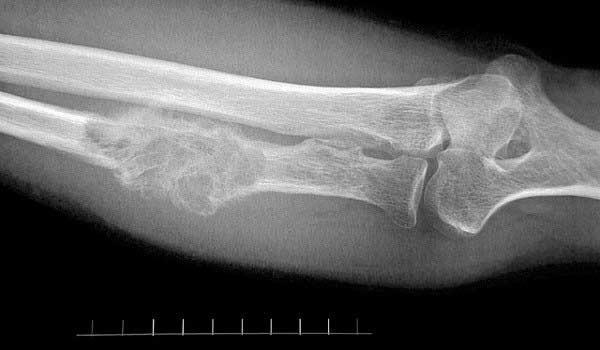

- Магнитно-резонансная томография (МРТ) шеи и основания черепа для оценки местного распространения.

- Компьютерная томография (КТ) с контрастированием для оценки костных структур и лимфатических узлов.

- Позитронно-эмиссионная томография/компьютерная томография (ПЭТ/КТ) всего тела для выявления отдаленных метастазов и точного стадирования.